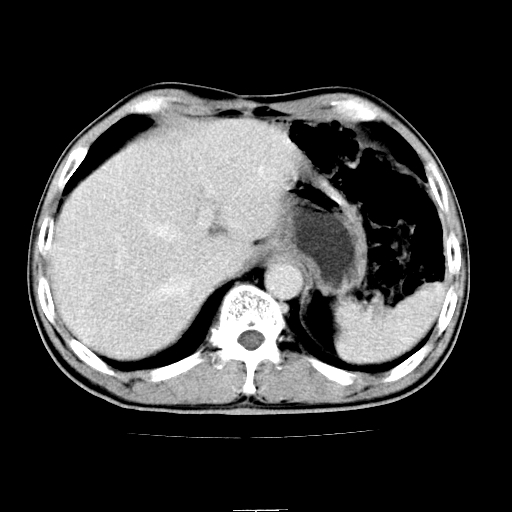

患者男,64岁,胃癌术后三个月,无明显不适。请讨论一下胰头前方小圆形低密度影为淋巴结还是肠管?

增强第6幅图上有气液平相通,是肠管,右肾低密度灶形态不规则似有壁结节,不除外转移.

应该考虑是肠管,理由1、平扫和增强对比,形态和内部的密度有明显改变。2、增强图片可见明显气液平面。

另外,胰腺体部密度在平扫和增强时均不太均匀,似有数个小的囊状低密度区存在。不知道增强时其他期如何?应该高度警惕为转移性病变。

胰头右侧低密度影卡考虑为肠管;胰头前部低密度影,增强环形强化,结合临床首先考虑转移灶,其次考虑淋巴结结核(中心干酪性坏死)。